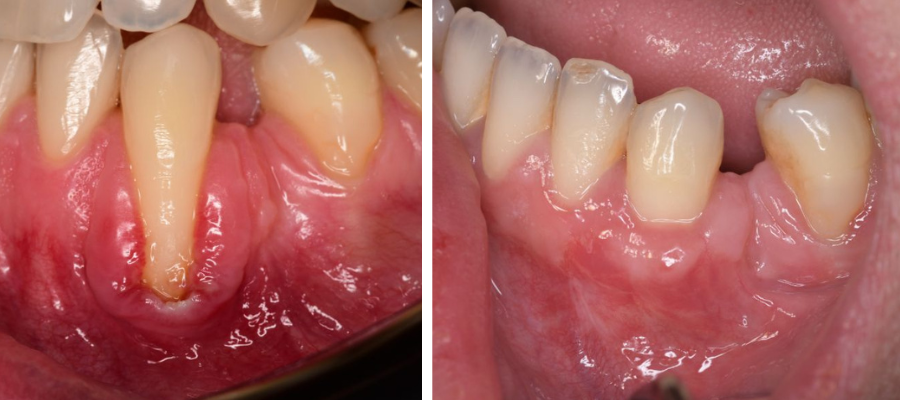

Parodontologija i kirurgija

Parodontologija je grana dentalne medicine koja se bavi zdravljem potpornih struktura zuba (parodonta). Parodont se sastoji od zubnog mesa (gingiva), kosti i vlakana koja vežu zub za kost (parodontalni ligament).

Ovo je grana kojoj Marković Dental Clinic pridaje puno pažnje jer je vrlo kompleksna i bitna za cijelo oralno zdravlje.

Regeneracija kosti i mekog tkiva

Gingivalne recesije u narodu poznatije kao „povlačenje zubnog mesa" moguće je korigirati kirurškim zahvatom te vratiti gingivu (zubno meso) u fiziološki položaj mikrokirurškim tehnikama. Zahvati koje odrađujemo kod regeneracije kosti i mekog tkiva su podizanje dna sinusa (sinus lift) i nadomještanje izgubljenog volumena kosti (augmentacija kosti, regeneracija kosti).